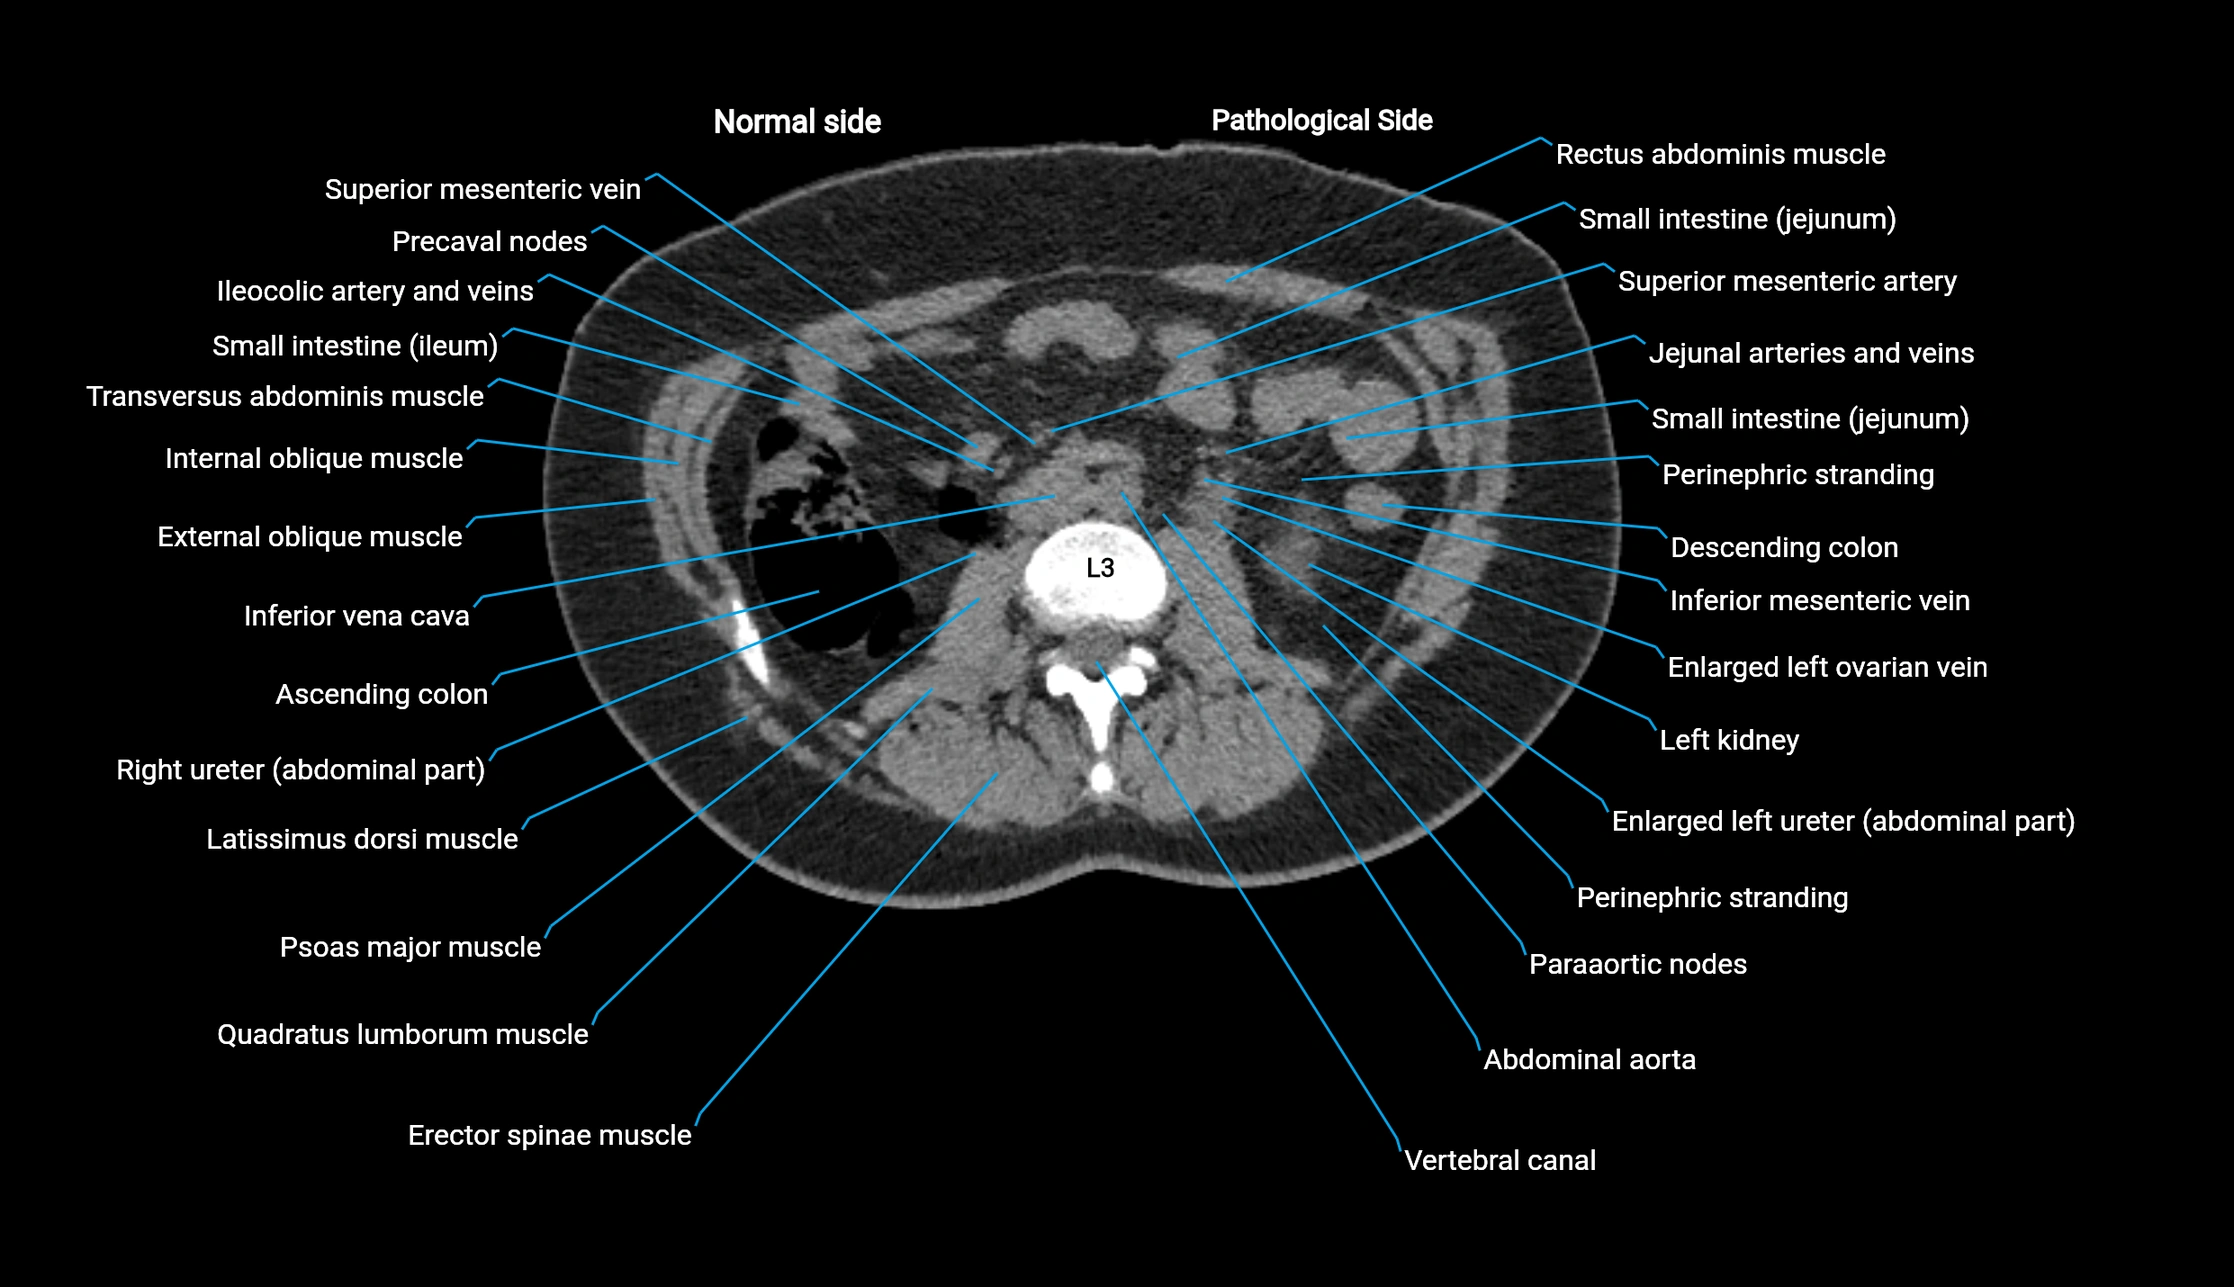

CT image

image